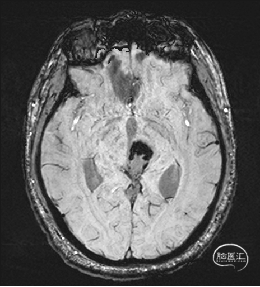

术前MRI检查

术前MRI检查提示左侧丘脑中脑海绵状血管瘤并卒中,梗阻性脑积水;

根据MRI及DTI显示,只有在丘脑与上丘之间的点(dot)进入病变才可能在切除病变时最大程度保护神经功能,由于上述原因,该“点”在术中显露极其困难,虽有导航指引,电生理监测的条件下,对术者的耐心、技术、经验及体能依然是极大的挑战;

本例患者磁共振检查清晰显示病变位于左侧丘脑中脑区域,且位于丘脑内下方向中脑顶盖延续,病变的上部、前部、外侧部都有重要的神经组织,因此,手术从上方、前方、外侧方向切除病变均难以实施;

术前详细的磁共振检查,包括平扫增强,SWI及DTI,可以规划出手术最适宜的路径及切入点;